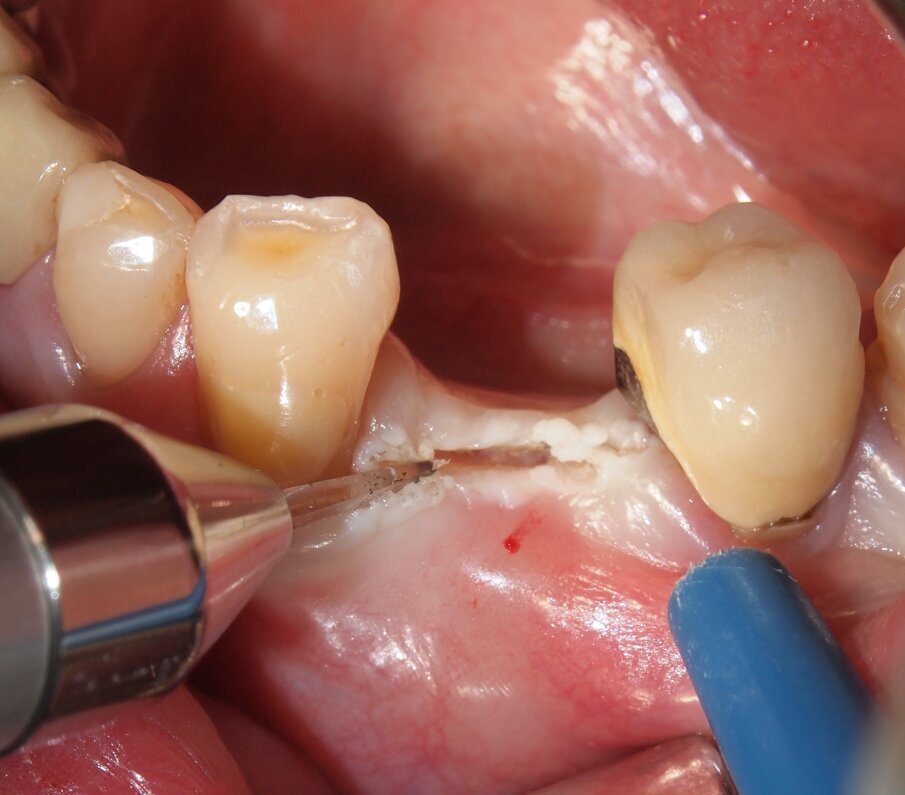

Fig. 6 - Caso clinico 1. Sollevamento di un lembo mucoperiosteo ed esposizione della corticale ossea. Si apprezza macroscopicamente l’assenza di fenomeni di carbonizzazione e danni termici dei tessuti molli e del tessuto osseo che mantiene un’adeguata vascolarizzazione.

Fig. 7 - Caso clinico 1. Posizionamento di una fixture di dimensioni adeguate al caso clinico in esame.